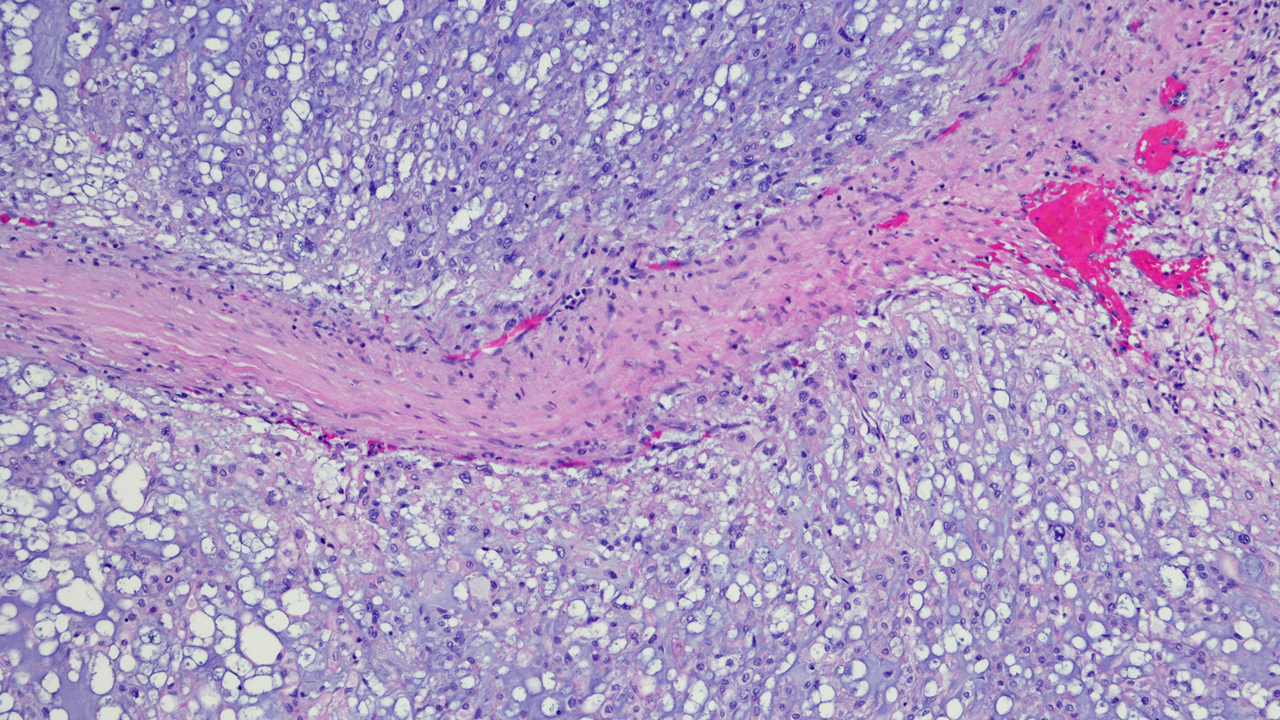

Chordomas are rare tumors that occur in one out of one million people. They are malignant tumors that tend to grow slowly and can spread to other parts of the body.

Chordoma tumors develop from cells of a tissue called the notochord and can occur anywhere along the spine, from the base of the skull to the tailbone.

Consider a dandelion: When you blow the seeds, they self-plant and begin to grow where they land. Likewise, a chordoma is one of the few tumors that can “seed” its cells to surrounding tissues. If a tumor is ruptured in surgery, tumor cells will spill into surrounding areas, planting new seeds that will grow into new tumors.